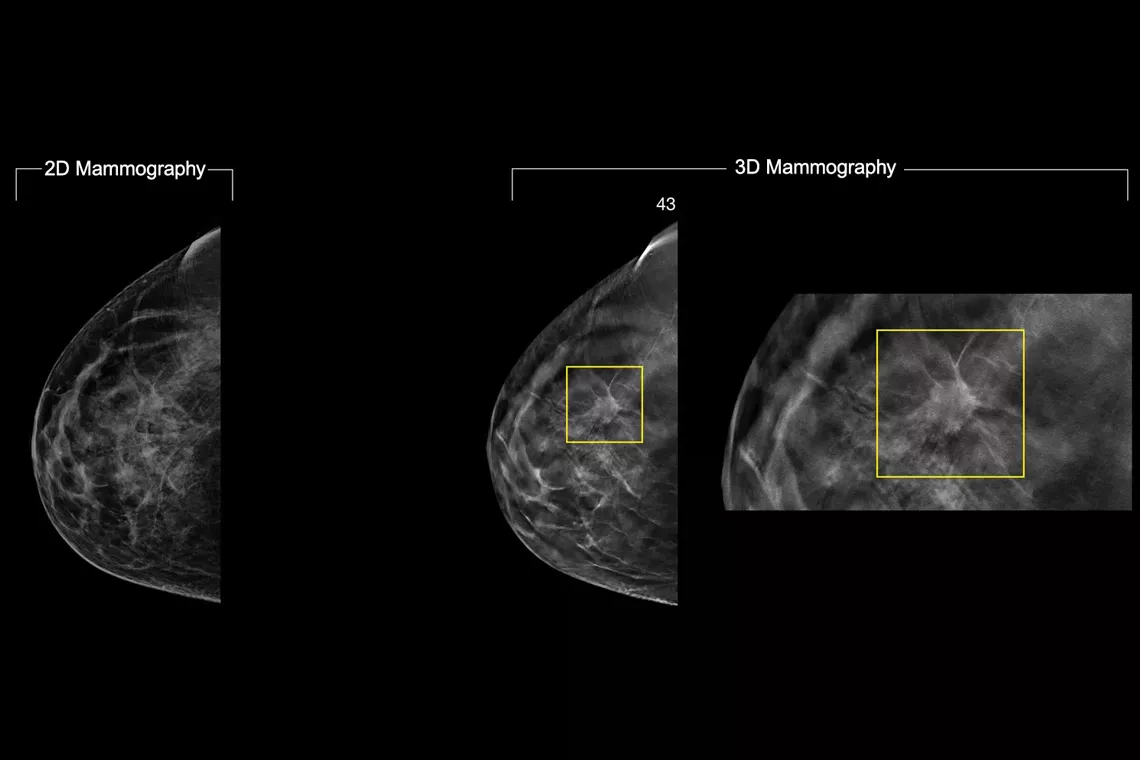

In a constantly changing clinical mammography environment, the flexibility and compatibility of ImageChecker 2D CAD Technology provides detection for conventional 2D images, as well as C-View™ and Intelligent 2D™ synthesised images derived from a tomosynthesis dataset.

ImageChecker 2D CAD Technology searches digital mammograms for potential microcalcifications and masses, characteristics commonly associated with breast cancer.

• Regions-of-interest are highlighted for the radiologist’s attention

• Delivers highly sensitive results without excessive false-positive marks, streamlining case review2

• Easy navigation to the slice of interest in the tomosynthesis stack, when used in combination with Smart Mapping on synthesized 2D images

Digital mammography with peer emphasize marks